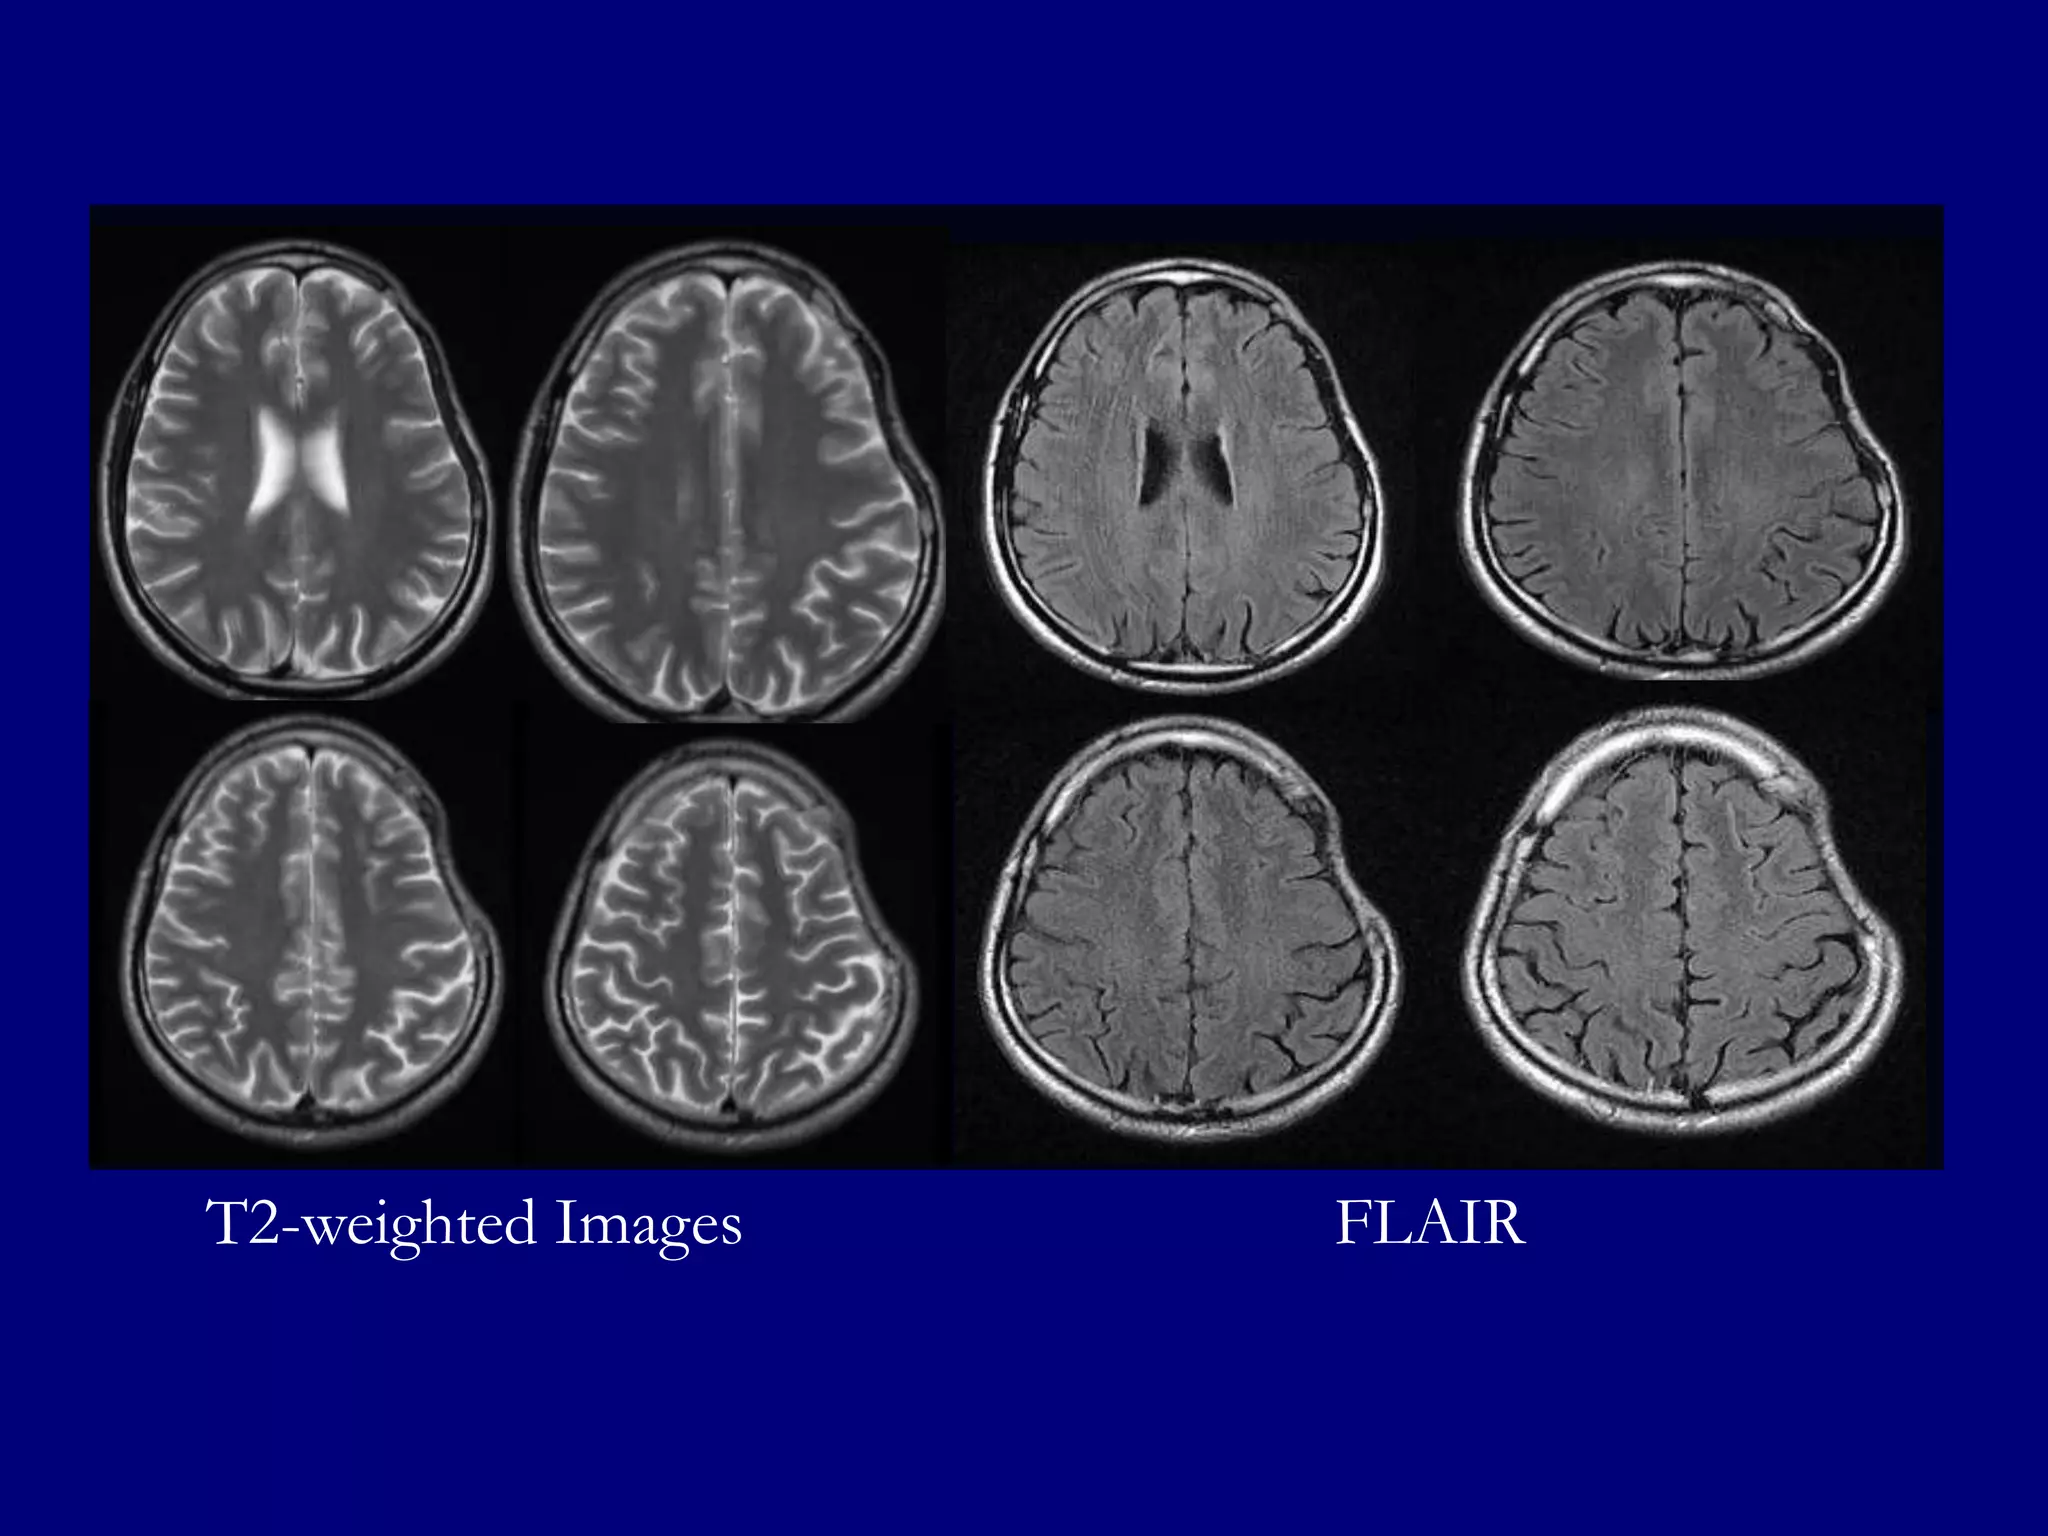

FLAIR: Well defined hyperintense lesions in the left fronto-parietal lobes with

hyperintensities in left basal ganglia, splenium of corpus callosum and left cerebellum